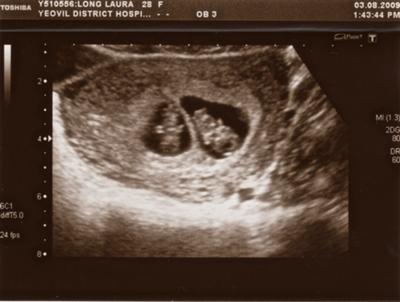

вижу 1 плодное яйцо...вот как двойни выглядят(1 фото 4 недели)(второе 6 недель)